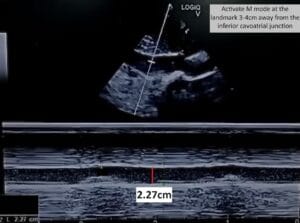

The IVC maximal diameter improved to approximately 2.1 cm, with >50% inspiratory collapse with an estimated right atrial pressure of 8 mmHg (Figure 5). Follow up POCUS after the third session demonstrated further improvement in IVC size (<2 cm), and collapsibility consistent with an estimated right atrial pressure of 3 mmHg (Figure 6). Remarkably, the shape of the IVC shifted from circular to oval during the decongestion of the patient, which is a clinically useful qualitative parameter. Hepatic vein Doppler demonstrated further improvement in S-wave amplitude to near-normal configuration, and the portal vein remained continuous (Figure 7). Intrarenal venous Doppler was not performed, as it is unreliable in ESKD.

Figure 5. Inferior vena cava ultrasound short axis demonstrating the maximal anteroposterior diameter (approximately 2.1 cm) and inspiratory collapse.

Figure 6. Inferior vena cava ultrasound short axis demonstrating the maximal anteroposterior diameter (approximately 1.9 cm) and inspiratory collapse.